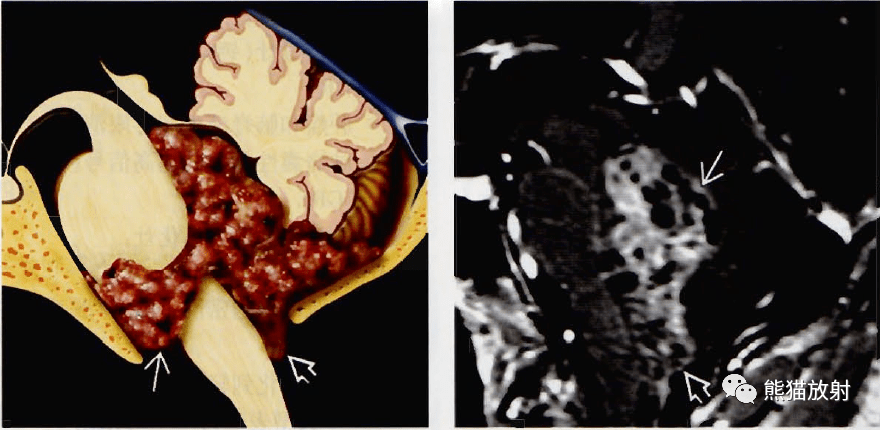

幕下幕上室管膜瘤室管膜下瘤丨影像诊断要点

图片尺寸880x430